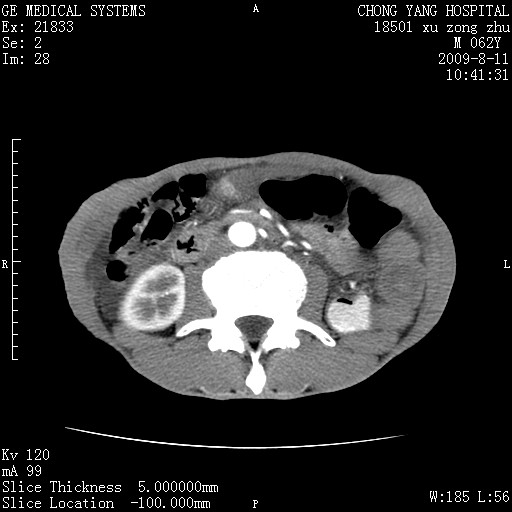

以下是引用杀毒软件在2009-8-11 16:35:00的发言:[br]肝内胆管扩张局限于左叶,胆管内有结石伴肝外胆管结石,胆管壁增厚呈弥漫性并发腹腔积液,胰腺边界模糊。[br][br]考虑---胆总管及肝内胆管结石继发胆管炎及胰腺炎,左肾下极囊肿,腹水。

以下是引用zjzjr在2009-8-11 17:35:00的发言:[br]肝内胆管扩张局限于左叶,胆管内有结石伴肝外胆管结石,胆管壁增厚呈弥漫性并发腹腔积液。[br][br]考虑---胆总管及肝内胆管结石继发胆管炎,左肾下极囊肿,腹水。